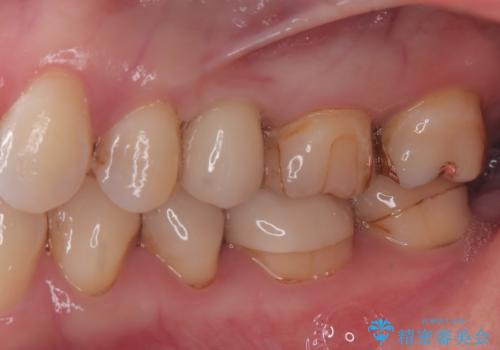

今回の症例では、骨の量が十分あったため、比較的短期間で治療を完了することができました。インプラントを使用することで、安定した咬み合わせが実現し、患者様は痛みもなく安心して食事を楽しむことができるようになりました。

インプラント治療は、しっかりとした診断と計画のもとに行われることで、自然な見た目と快適な噛み心地を取り戻すことができます。もし、歯を失ってお困りの方や、他の治療法で満足していない方がいらっしゃいましたら、ぜひ一度ご相談ください。